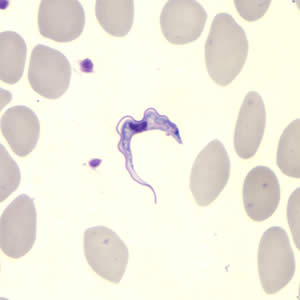

T. gambiense and T.rhodesiense